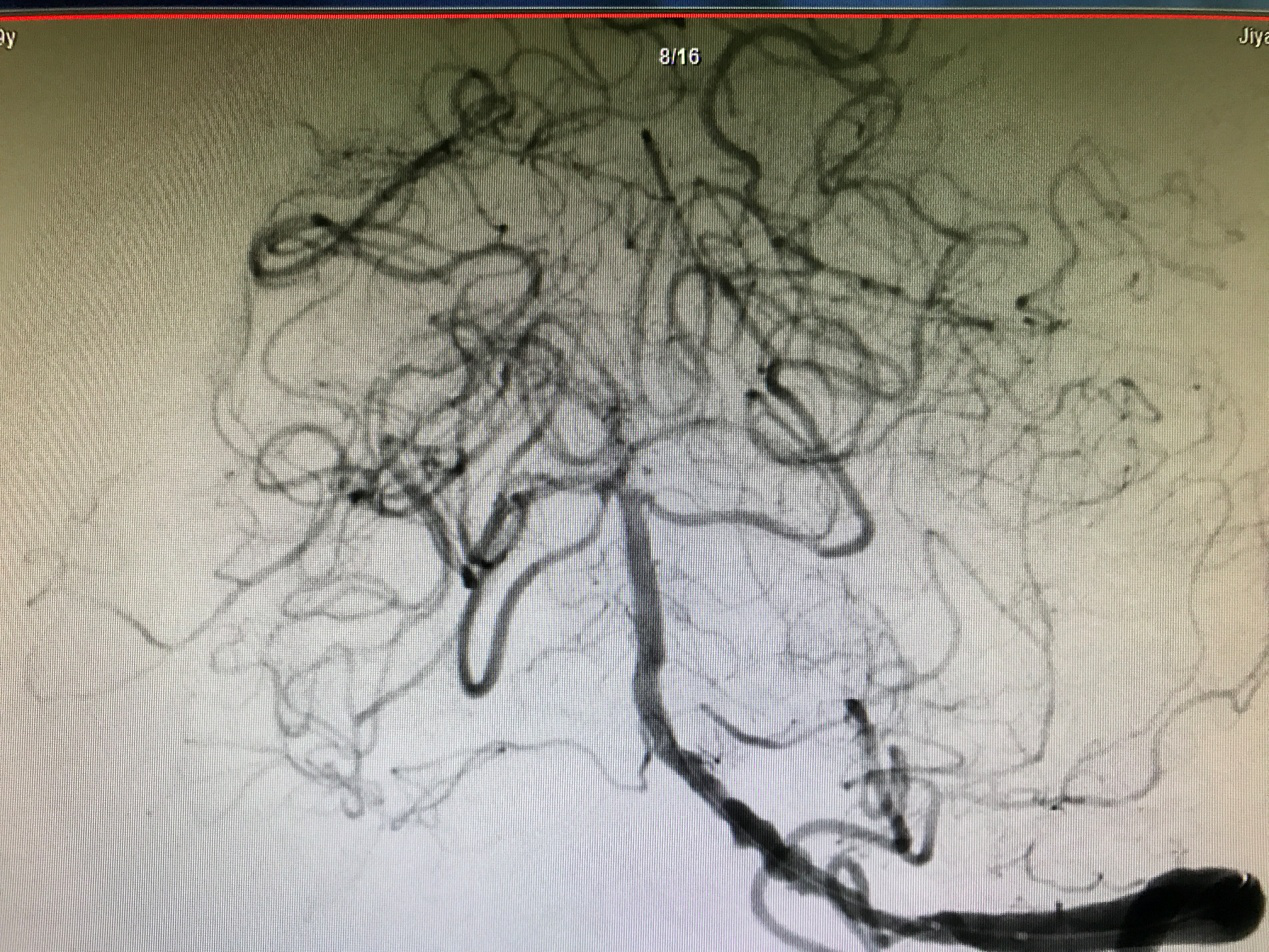

图 3 支架术后

如此程度的脑血管狭窄,仅凭药物治疗是无效的,经过严密而谨慎的评估,神经内二科主任高磊决定为患者实施基底动脉支架成形术。就是在血管狭窄的地方放置一枚支架将狭窄的血管撑开,让脑血流更加通畅一些,从而改善脑部的血液供应。这个病人支架手术的最大困难和挑战在于既要在血管狭窄段成功放置支架,又要保护狭窄处基底动脉的重要血管分支不因为放置支架而闭塞,从而引起新的脑梗死。经过严密的术前准备,成功为患者实施了基底动脉支架,术后造影显示基底动脉狭窄消除,血管分支保护良好(如图3所示)。